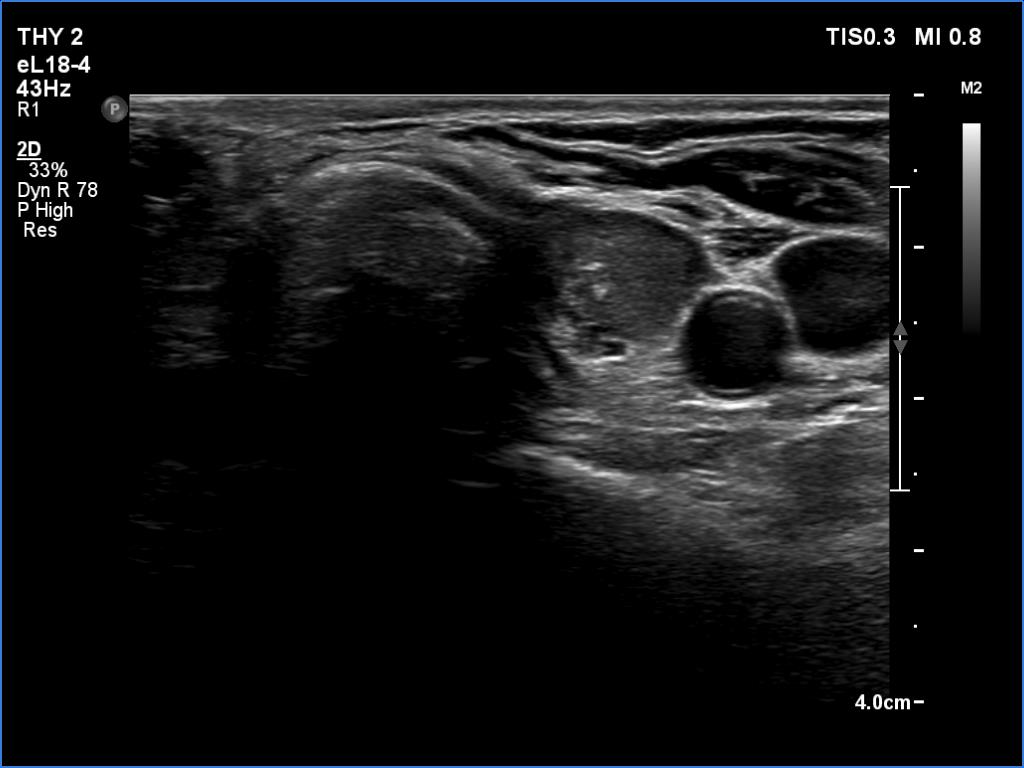

Second examination (second row of images):

Clinical data: The patient came to a routine follow-up.

Palpation: no abnormality.

Laboratory tests: TSH 3.84 mIU/L on daily 75 microgram levothyroxine.

Ultrasonography. The presentation of the thyroid was essentially the same. The mass in question became smaller. This was avascular and proved to be hard on elastography.

A surgical procedure has a great and permanent impact on the ultrasound pattern and results in discrete lesions on ultrasound. It is very unlikely that years after the surgery, true nodules will evolve in a patient who previously had non-nodular thyroid on histopathology. The patient' history is of the greatest help in such cases to avoid overinterpretation of discrete lesions.

A granulation around surgical thread is always avascular. This is usually presented as an echonormal, irregularly shaped mass which has echogenic granules. It is almost always hard on palpation.